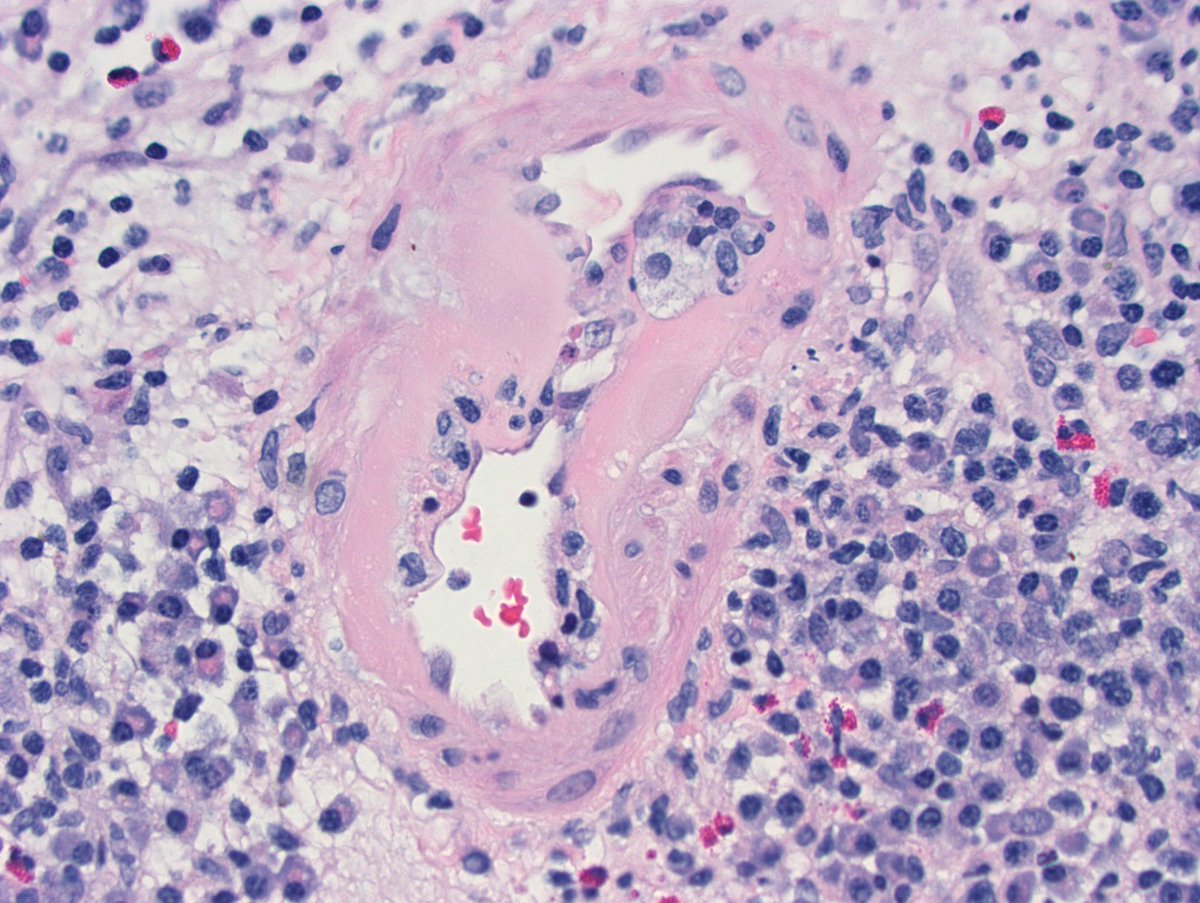

Long weekend often brings urgent cases. Here is one that was STATed, ended up showing anti-GBM GN. Diffuse crescents (nearly 100%). Linear IgG. #RenalPath